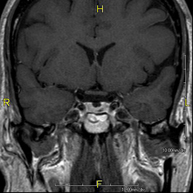

- RM Cerebral (cranial)

Prova diagnòstica no invasiva que consisteix en l'obtenció d'imatges d'alta definició anatòmica del cerbell mitjançant l'ús d'un camp electromagnètic i ones de ràdio (com un emissor i un receptor). No utilitza radiació ionitzant. Indicacions: problemes vasculars, pèrdua de memòria, epilèpsia, cefalea, malformacions, sospita de tumor, meningitis. - RM de Cais

Prova diagnòstica no invasiva que consisteix en l'obtenció d'imatges d'alta definició anatòmica del cervell mitjançant l'ús d'un camp electromagnètic i ones de ràdio (com un emissor i un receptor). No utilitza radiació ionitzant. Posteriorment es realitza una mesura qualitativa i quantitativa de diversos metabòlits (substàncies) que permetran caracteritzar les lesions. Indicacions: tumors, trastorns metabòlics, infeccions, epilèpsia.

Prova diagnòstica no invasiva que consisteix en l'obtenció d'imatges d'alta definició anatòmica de la hipòfisi cerebral mitjançant l'ús d'un camp electromagnètic i ones de ràdio (amb un emissor i un receptor). No utilitza radiació ionitzant. Indicacions: trastorn del creixement, trastorns hormonals, tumors. - RM de Sins paranasals